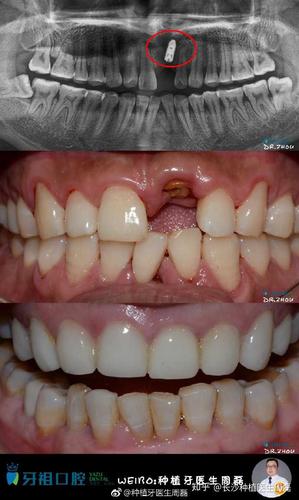

单颗种植牙修复前后的效果图

种植牙前后对比照片